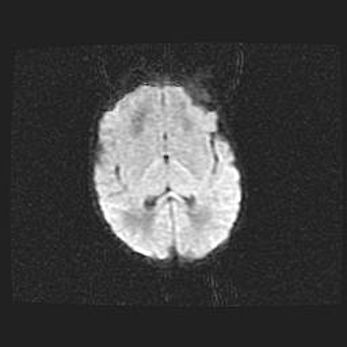

Множественные кисты обоих полушарий головного мозга, наибольшая из них в правой затылочной области. Ассиметричная атрофическая гидроцефалия.

Возраст: 7 месяцев

Вес: 5660 г

Пол: мужской

Окружность головы: 41,5 см

Срок гестации: 28-29 недель

Кисты головного мозга развиваются в результате многоочаговых некрозов вещества мозга и возникают вследствие перенесенной перинатальной инфекции, менингитов, энцефалитов, асфиксии, родовой травмы, расстройств мозгового кровообращения различного генеза. Образованию кист в веществе головного мозга плодов и новорожденных способствуют такие факторы, как высокое содержание в нем воды, недостаточная (или отсутствие) миелинизация и слабая астроглиальная реакция на повреждение.

Кисты могут сочетаться с гидроцефалией и другими поражениями головного мозга.